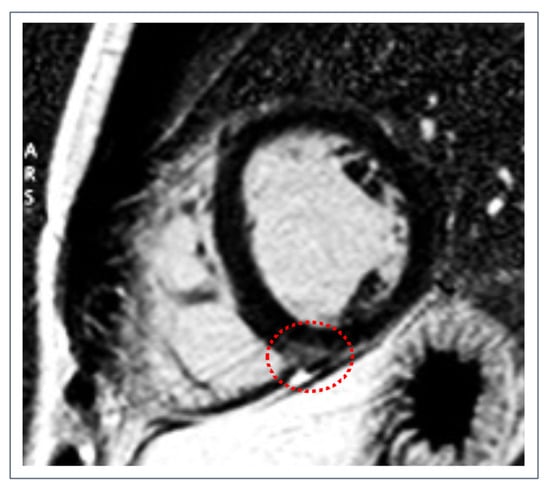

- Petersen, S.E.; Selvanayagam, J.B.; Wiesmann, F.; Robson, M.D.; Francis, J.M.; Anderson, R.H.; Watkins, H.; Neubauer, S. Left ventricular non-compaction: Insights from cardiovascular magnetic resonance imaging. J. Am. Coll. Cardiol. 2005, 46, 101–105. [Google Scholar] [CrossRef]

- Jacquier, A.; Thuny, F.; Jop, B.; Giorgi, R.; Cohen, F.; Gaubert, J.-Y.; Vidal, V.; Bartoli, J.M.; Habib, G.; Moulin, G. Measurement of trabeculated left ventricular mass using cardiac magnetic resonance imaging in the diagnosis of left ventricular non-compaction. Eur. Heart J. 2010, 31, 1098–1104. [Google Scholar] [CrossRef] [PubMed]

- Gati, S.; Chandra, N.; Bennett, R.L.E.; Reed, M.; Kervio, G.; Panoulas, V.F.; Ghani, S.; Sheikh, N.; Zaidi, A.; Wilson, M.; et al. Increased left ventricular trabeculation in highly trained athletes: Do we need more stringent criteria for the diagnosis of left ventricular non-compaction in athletes? Heart 2013, 99, 401–408. [Google Scholar] [CrossRef] [PubMed]

- Caselli, S.; Ferreira, D.; Kanawati, E.; Di Paolo, F.; Pisicchio, C.; Jost, C.A.; Spataro, A.; Jenni, R.; Pelliccia, A. Prominent left ventricular trabeculations in competitive athletes: A proposal for risk stratification and management. Int. J. Cardiol. 2016, 223, 590–595. [Google Scholar] [CrossRef]